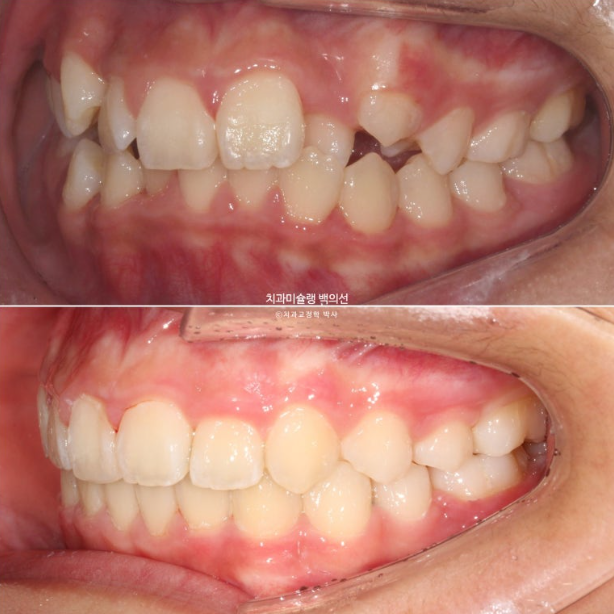

24년 1월 교정치료를 위해 온 만 10세 어린이입니다.

24.02

3년 전에 소아치과에서 앞니 부분교정을 한 적이 있다고 합니다.

그래서 위 앞니에는 중절치 두 개를 잇는 철사유지장치가 붙어있었습니다.

중심선이 약 2mm 어긋나 있고 위 앞니 치축은 한쪽으로 기울어져 있습니다.

앞니가 깊게 물리는 과개교합도 보입니다.

공간부족으로 인한 덧니가 심해 반대교합이 있습니다.

24.02~25.07

어긋난 중심선이 맞아졌으며 기울어진 앞니 치축도 좋아졌습니다.

앞니가 깊게 물리는 과개교합도 좋아졌습니다.